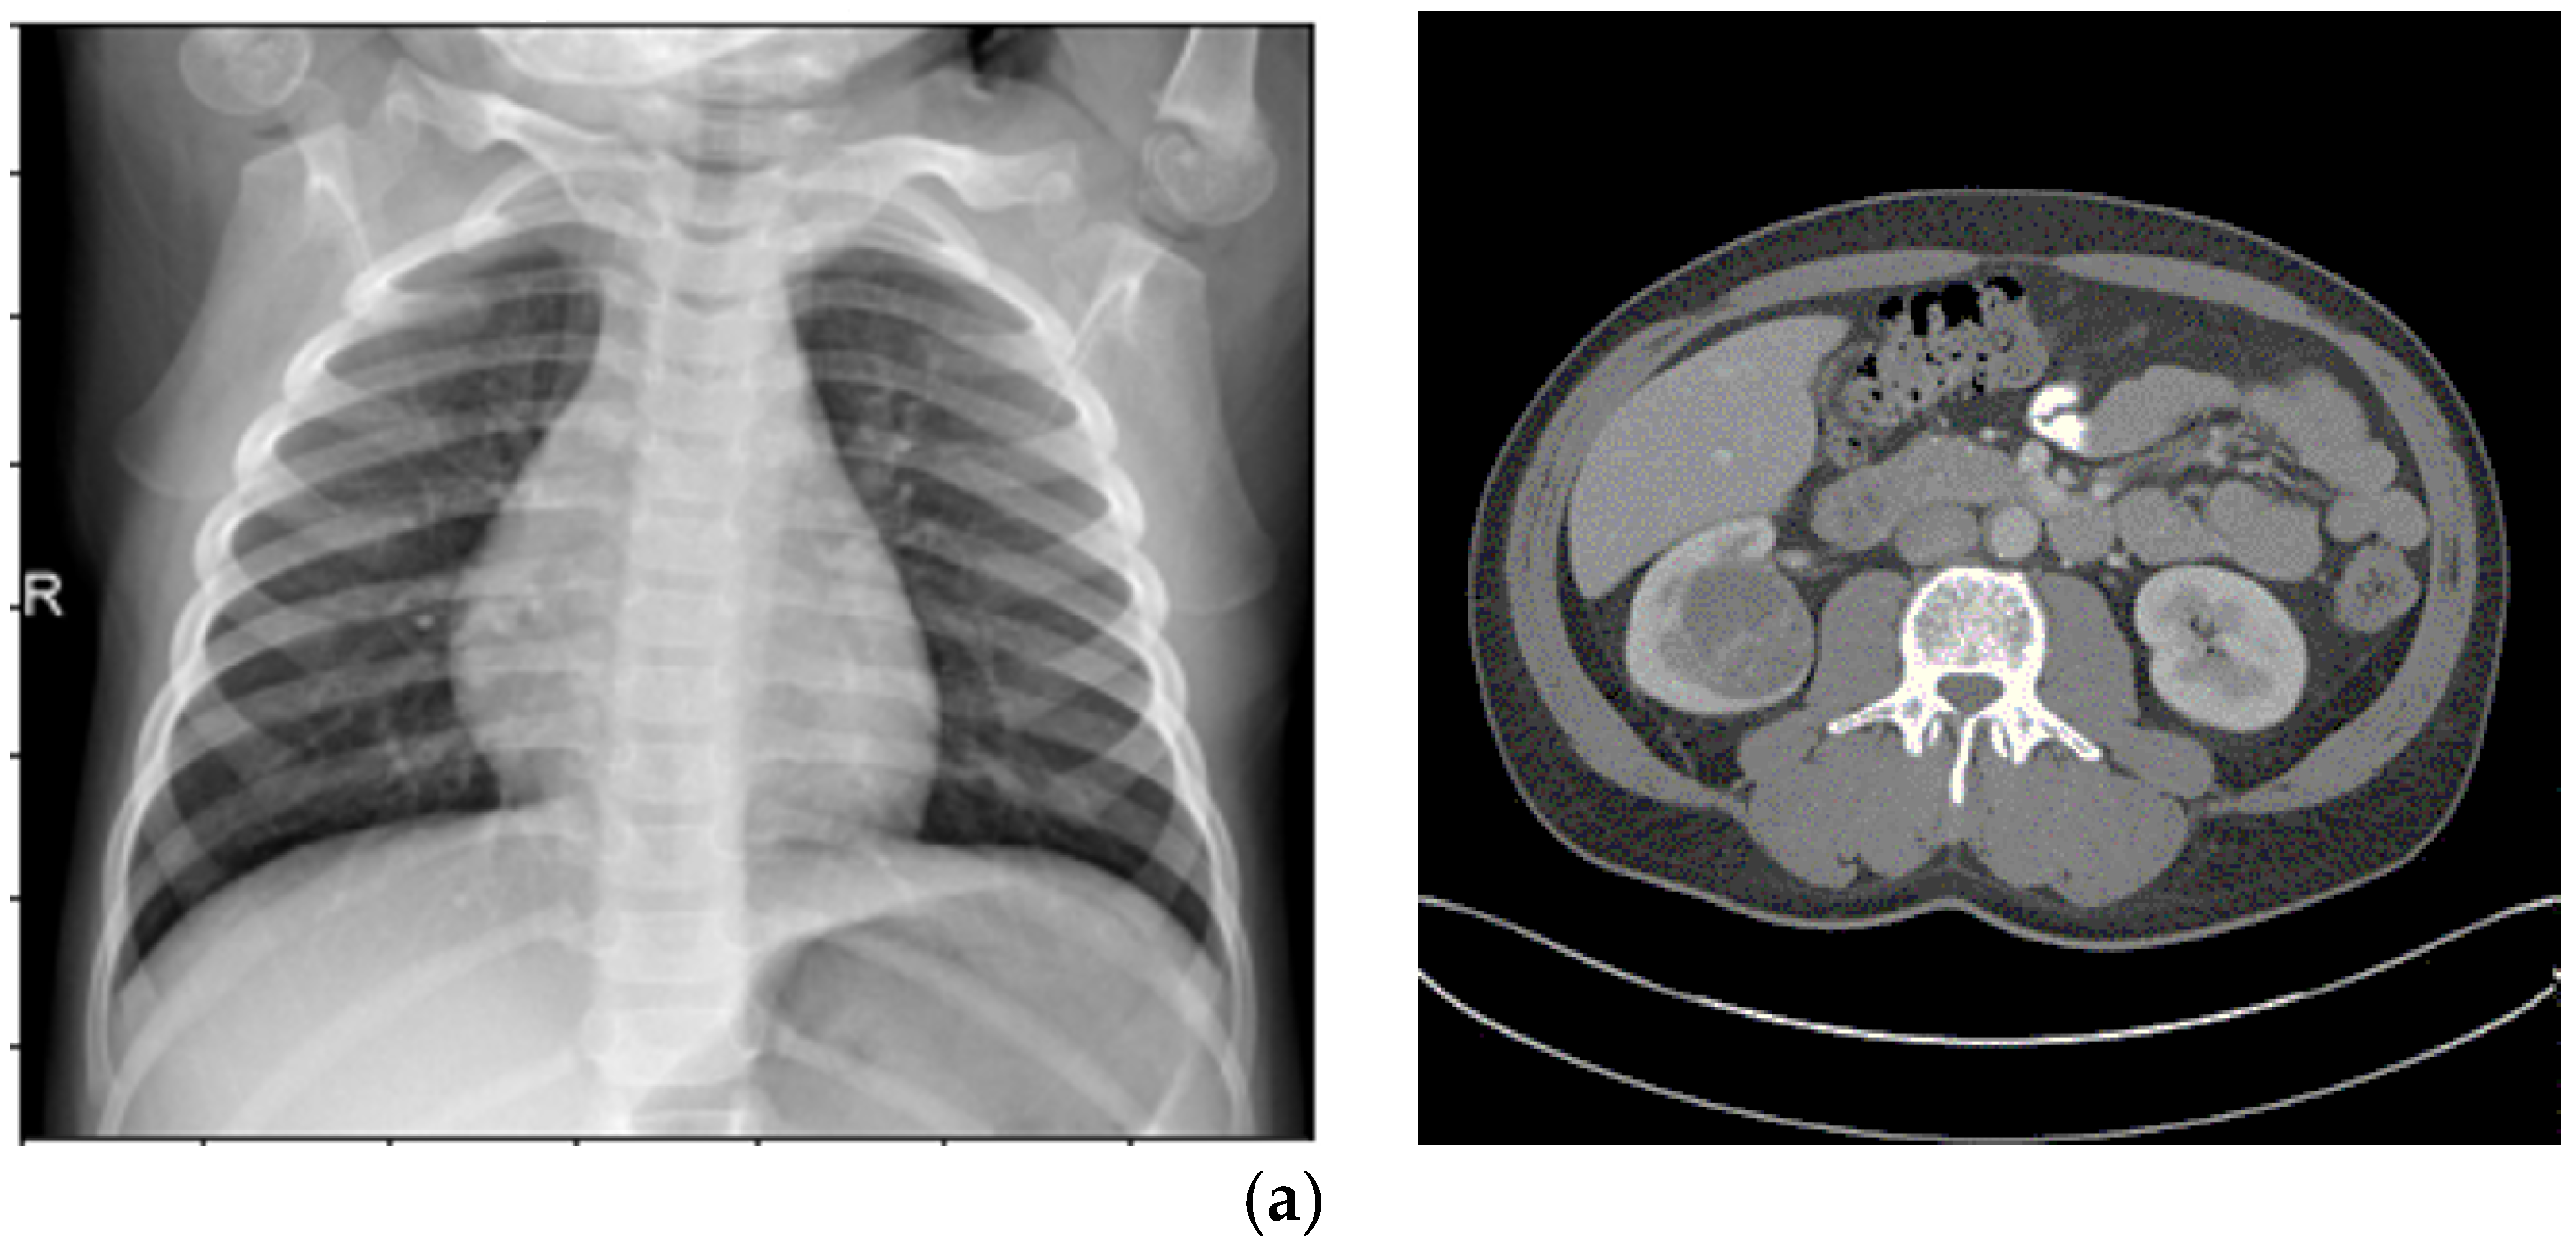

4.1.1. KiTS19

210 training and 90 test instances of 3D CT scans with annotations for kidney and tumor regions make up the Kidney Tumor Segmentation 2019 (KiTS19) dataset, which was obtained from Kaggle. https://www.kaggle.com/datasets/sabahesaraki/kidney-tumor-segmentation-challengekits-19/data (accessed on 15 September 2025).

This dataset serves as a standard for assessing automated segmentation algorithms in clinical settings and is intended for the semantic segmentation of kidneys and malignancies. The CT scans are appropriate for evaluating the enhancement pipeline’s capacity to increase contrast and lower noise in soft tissue areas since they provide comprehensive anatomical structures. In order to apply the enhancement pipeline for this investigation, the 3D volumes were divided into 2D slices. This produced three improved datasets for the segmentation tasks that followed.

4.3.3. Segmentation Performance (KiTS19)

The original dataset (300 cases) and the improved datasets (900 cases total: 300 × 3) were used to train the two CNN models for the KiTS19 dataset. The improved datasets were used to train CCNN, and the fuzzy entropy-based dataset produced the best-performing model (BRISQUE: 23.1). Dice coefficient, accuracy, precision, sensitivity, and recall were used to assess performance. The BRISQUE scores and segmentation accuracy of the three models are contrasted in Table 4.

Both the original and CLAHE-filtered datasets fared worse than the suggested enhancement pipeline. The BRISQUE score of the original KiTS19 dataset was 28.8, but CLAHE raised it to 26.4. Our approach produced better image quality with a lower BRISQUE score of 21.7. The significant influence of our enhancement strategy on segmentation performance was demonstrated by the CCNN model trained on our enhanced dataset, which achieved an accuracy of 0.983, a 2.4% improvement over the CLAHE-filtered dataset (0.959), and a 6.2% improvement over the original dataset (0.921). Figure 5 includes a sample visualization of the segmentation results.